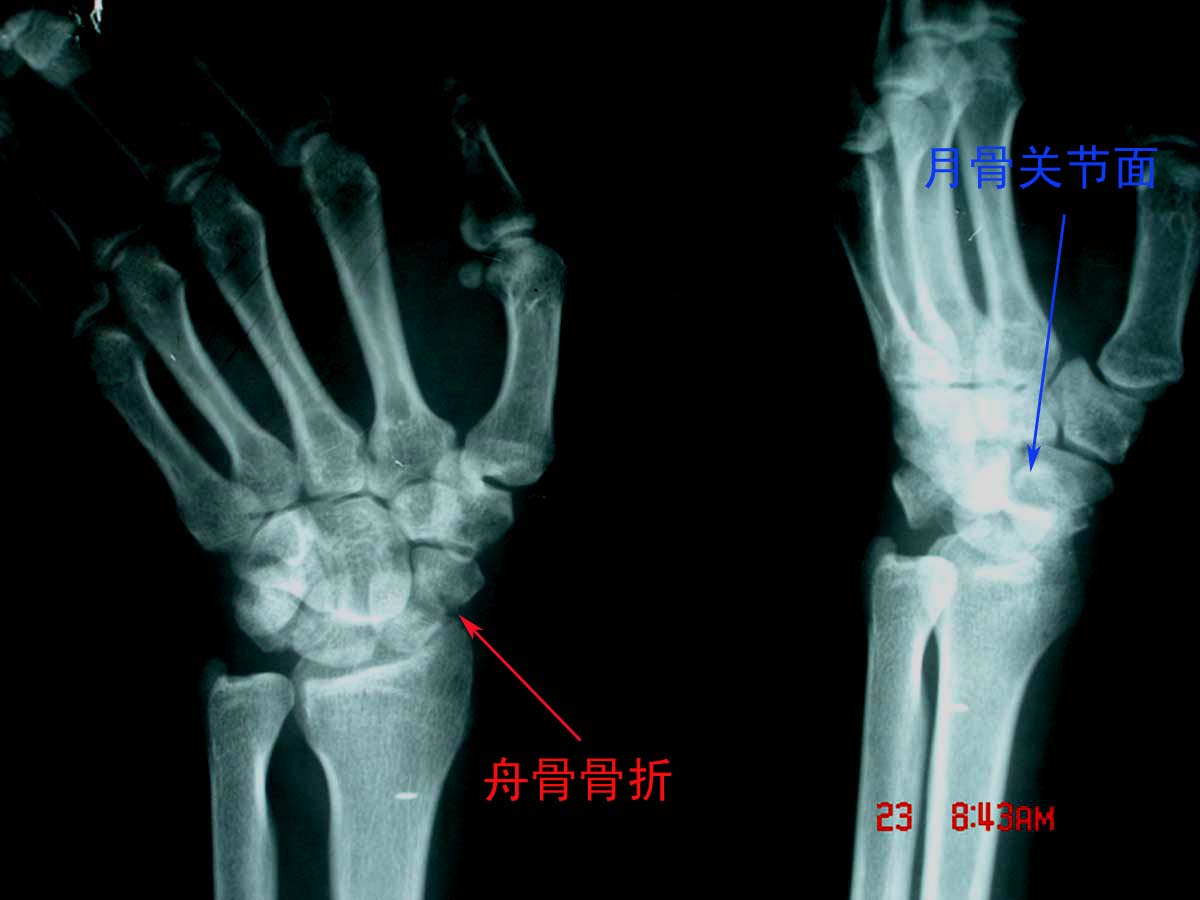

男,36岁,外伤后左腕部肿痛2小时。

左舟骨骨折伴有左月骨半脱位。

考虑:1、左舟骨骨折;

2、月骨半脱位;

3、软组织内金属异物。

此例我感觉是“经舟骨月骨周围脱位”,我曾发布过一例,如下图:

下面一例“月骨脱位病例”,请大家比较一下:

我赞同是1、“经舟骨月骨周围脱位”,表现为月骨周围脱位拌舟骨骨折,且骨折远段随头骨向后脱位,而骨折近段与桡骨、月骨关系保持正常。2、软组织内金属异物。